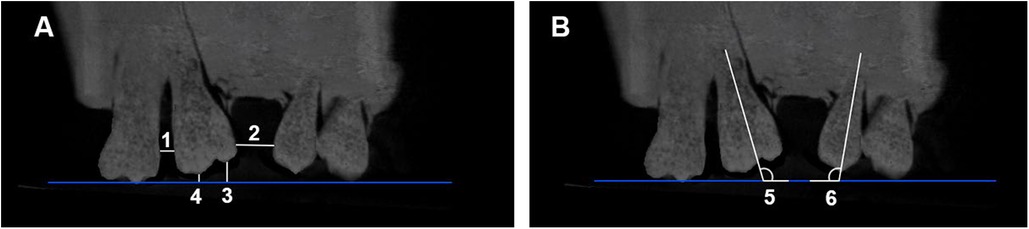

Four linear and two angular measurements (Table 1 and Figure 5) were performed using Dolphin 3D software (Dolphin Imaging 11.0, Dolphin Imaging and Management Solutions, Chatsworth, CA) to assess the type and extent of tooth movement in each group. To ensure methodological reliability, the full experimental protocol was repeated ten times per group.

Figure 5. (A) The linear and (B) angular measurements selected in the study. (1) UL7—UL6 (mm), (2) UL6—UL4 (mm), (3) UL6 MC—OP (mm), (4) UL6 DC—OP (mm), (5) UL6—OP°, and 6) UL4—OP°.